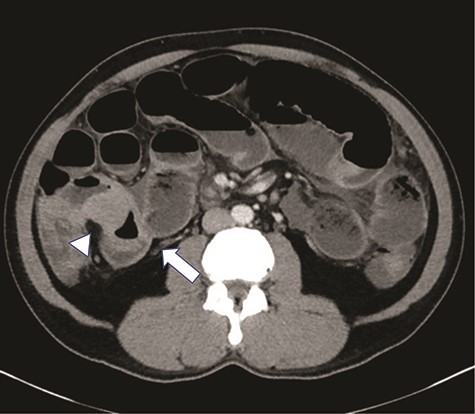

A 47-year-old male presented to the Emergency Department with abdominal pain, nausea, emesis and diarrhea for four days. His last bowel movement was the day prior and he was continuing to pass flatus. On physical examination, his abdomen was soft and nondistended, with tenderness in the epigastrium and left lower quadrant. His vital signs and laboratory values were within normal limits. Computerized topography (CT) scan showed a high-grade SBO with a transition point within distal ileum with asymmetric irregular bowel wall thickening, which was suggestive of a mass (Fig. 1). A moderate amount of ascites was also noted, as well as an appendicolith within the appendix, mildly thickened to 8 mm without any other sign of inflammation (Fig. 2). The patient was admitted to the hospital for initial conservative management, and a cancer work up was initiated for a primary SBO. CT of the chest showed no distant metastases. Tumor markers (carbohydrate antigen 19–9, carcinoembryonic antigen and alpha-fetoprotein) were all within normal limits. Over the next three days, the patient regained bowel function and his pain improved. He opted for outpatient colonoscopy and surgery and was discharged home. Two days later, the patient represented to the ED with abdominal pain, distention and emesis. He had a normal white blood cell count with neutrophilia and lactic acidosis of 3.1. A repeat CT scan of the abdomen and pelvis showed essentially unchanged findings from the prior study. He then was taken to the operating room for exploratory laparotomy. A firm mass was noted 20 cm proximal to the terminal ileum with a mass lesion and an abnormal, firm appendix. We performed a small bowel resection and appendectomy. The patient was subsequently referred to the hematology/oncology department for further treatment. He underwent a bone marrow biopsy which was negative for evidence of leukemia and subsequently began treatment with induction chemotherapy.

High grade SBO with a transition point within the right lower quadrant in distal ileum (arrow). The bowel loop in this region demonstrates significantly asymmetric irregular wall thickening (arrowhead).